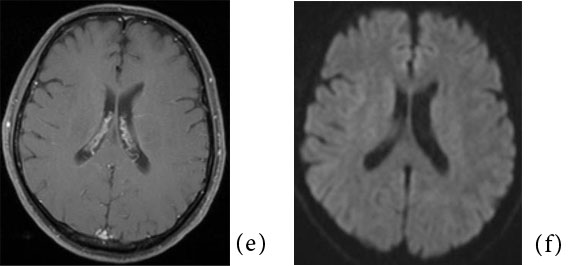

MRI では、T2 強調像および拡散強調像にて 脳梁膨大部中間層に円形もしくは卵円形の高信 号を呈する領域を認め、T1 強調像にて淡い低信 号もしくは等信号を呈する(Fig.1)。ADC map では一過性病変であるにも関わらず、急性期脳 梗塞など細胞障害性変化を来す疾患と同様に病 変部のADC 値は低下している。よって同じ一 過性病変である、高血圧脳症などいわゆるposterior reversible encephalopathy syndrome (PRES)や、高地脳症などにおける血管原性浮 腫とは異なる病態が存在する。このADC 値低 下の原因については軸索の表面を覆うミエリン 鞘の分離によって生じる軸索内浮腫2)が最も考 えられているが、まだコンセンサスは得られて いない。Takanashi らはMERS 患者に共通して 低ナトリウム血症を認めたと報告しており3)、 特に感染症においては嘔吐や下痢に伴う電解質バランスの破綻も関与している可能性がある4)。 異常信号は脳梁の他の部位や、白質に左右対称 性に及ぶこともある。通常は可逆性だが、時に 不可逆性の場合もある。造影MRI にて造影増強効果は認めない1) 5)

Fig.1 50 歳代、男性。軽度の意識レベル低下を認めたためにMRI が施行された。

(a,b):脳梁膨大部に卵円形の淡いT2WI 高信号、T1WI 低信号域を認める (矢印)。明らかなmass effect は認められない。

(c, d):同病変は拡散強調像にて高信号(矢印)、ADC map にて低値を示し (矢印)、拡散低下が示唆される。